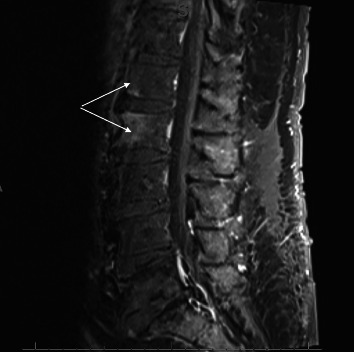

背景:尿气球菌是一种罕见的人类病原体,主要引起尿路感染、心内膜炎和菌血症。然而,它很少引起其他类型的感染,如脊柱炎。侵袭性尿支原体感染主要发生在有泌尿道疾病的老年男性中。实际发病率可能被低估了,因为气球菌生长在含二氧化碳的大气中,而尿液培养物通常不在这种环境中培养。有8例报告脊柱炎由尿单胞杆菌引起。材料和方法:我们报告了第9例发生在80岁的白人男性腰痛。患者有易感因素(糖尿病和泌尿外科手术史)。脊柱MRI显示脊椎椎间盘炎征象。两次针对椎间盘和腰肌的计算机断层引导活检没有诊断。10个血培养瓶中有一个培养出尿支原体。结果:在L2骨折恶化和不成功的经皮取样手术后,患者接受了T12至L4的手术稳定和多次活检。活检培养有尿气球菌。静脉滴注阿莫西林14天,口服左氧氟沙星3个月。结论:对于培养阴性的脊柱炎患者,尤其是有糖尿病和泌尿系统疾病的老年男性,应考虑尿支原体感染。

Background: Aerococcus urinae, a rare human pathogen, mainly causes urinary tract infection, endocarditis, and bacteremia. However, it is rarely the cause of other types of infection such as spondylodiscitis. Invasive A. urinae infection chiefly occurs in older men with underlying urinary tract disorders. The real incidence may be underestimated, as Aerococci grow in a CO2-containing atmosphere, and urine cultures are usually not incubated in this environment. There have been eight case reports of spondylodiscitis due to A. urinae. Material and Methods: We report a 9th case occurring in an 80-year-old Caucasian man with lower back pain. The patient had predisposing conditions (diabetes and a history of urological surgery). Spinal MRI showed signs of spondylodiscitis. Two computed tomography-guided biopsies targeting the intervertebral disc and psoas muscle were not diagnostic. One of 10 blood culture bottles grew A. urinae. Results: After worsening of an L2 fracture, and unsuccessful percutaneous sampling procedures, the patient underwent surgical stabilization of T12 to L4 with multiple biopsies. Biopsy cultures grew Aerococcus urinae. Amoxicillin was administered intravenously for 14 days, followed by oral levofloxacin for 3 months. Conclusion: A. urinae should be considered in spondylodiscitis with negative cultures, particularly in older men with diabetes and urological conditions.